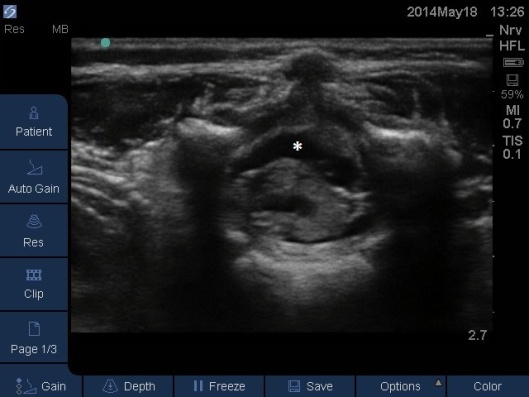

- The LA spread can be monitored to ensure it has spread high enough for the intended surgery. See Fig 11,12 and Video

- In neonates the probe can stay in the midline sagittal position, in older children it will be necessary to use the paramedian sagittal views (left and right) as the echo windows are greatest between the laminae. The probe moves synchronously cephalad as the LA spreads higher.

Fig 12. Ultrasound Probe in Midline Transverse position over the lumbar spine. White * indicates local anaesthetic seen as anechoic area in posterior epidural space.